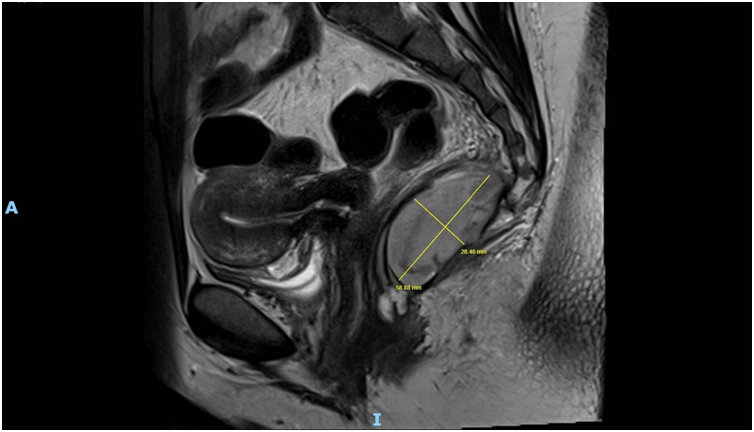

Imaging via MRI and CT demonstrated a complex, encapsulated lesion with peripheral enhancement and restricted diffusion. Multidisciplinary evaluation suggested a congenital epidermoid or duplication cyst. Given the absence of malignancy and surgical complexity, a conservative management strategy was adopted.

Figure 1: Figure 1 Duplication cyst 2025 MRI sagittal plane

Figure 2: Figure 2 Duplication cyst 2025 MRI sagittal plane